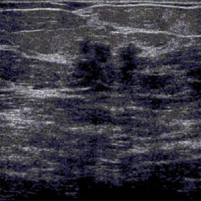

Although the proposed algorithm is independent of the imaging modality of the breast, we perform our simulations on ultrasound images, collected from the Radiology department, College of Medicine at the University of Illinois at Chicago. Our database of cancerous images show intraductal carcinoma, which is the most common type of breast cancer in women. Intraductal carcinoma is usually discovered through a mammogram or an ultrasound as microcalcifications. Our benign tumor images show the Fibroadenoma of the breast, which is a benign fibroepithelial tumor characterized by proliferation of both glandular and stromal elements.

We estimate the ARMA parameters using a window of size . The choice of the window size presents an inherent trade-off between the accuracy of the representation and the accuracy of the classification. A large window size would lead a better representation of the ARMA model, but might include pixels from different classes. We found that for images, a window size leads to a good segmentation performance. Figure 1 shows a cancerous image and a benign tumor image. Their ARMA representations are displayed in Figs. 1(b) and 1(e), respectively. It is visually clear that the ARMA model accurately represents both ultrasound images. Figures 1(c) and 1(f) show the segmentation outputs of the cancerous and benign tumor images, respectively. We can observe clear delineations of the tumors from the healthy tissues in both cases. Using the University of Illinois at Chicago’s database of ultrasound breast images, our method yields an accuracy (number of images correctly classified divided by the total number of images) of 82% (see Table 1).